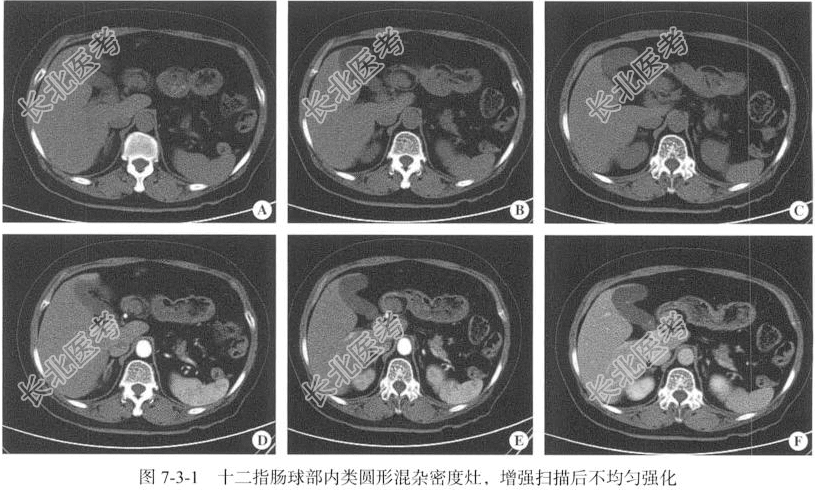

【影像图片】见图7-3-1。

【手术所见】肿物位于十二指肠球部,来源于黏膜下层,未浸透浆膜,游离度良好,大小约为4.00cm×3.00cm,质软,油腻。